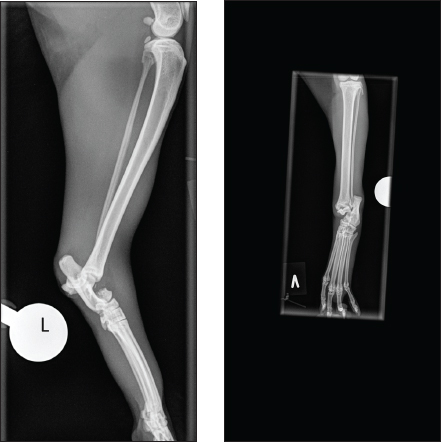

Eight weeks postoperatively, the cat was back for re-examination and radiographs. The owner reported that the cat moved freely around the house after 6 weeks of cage rest. The cat was anesthetized as previously, orthogonal radiographs revealed good fracture healing (Fig. 2a and 2b), and the lateral frame was removed according to standard procedures (Kraus et al., 2003). Twelve weeks postoperatively, the cat was back for re-examination and radiographs, and the owner could report that the cat was doing fine. The cat was anesthetized as previously for orthogonal radiographs, which revealed good fracture healing, and the medial frame was removed. A set of new orthogonal radiographs was taken after frame removal. Palpation of the affected talocrural joint revealed a moderately reduced range of motion (ROM) compared to the opposite joint. Measurements with a goniometer showed left extension at 160°, flexion at 67°, right extension at 167°, and flexion at 20° (Jaeger et al., 2007). Thirty-three weeks postoperatively, the cat was seen for a progress check. The cat was still not allowed outdoors. Slight lameness was evident when the cat moved freely on the floor. There was no pain or swelling in the affected area during palpation, and the ROM had improved, but it was still reduced compared to the opposite limb (left extension 163° and flexion 30°). The cat was anesthetized as previously for orthogonal radiographs (Fig. 3a and 3b).

Fig. 3. (A and B) Mediolateral and craniocaudal digital radiographs of the left hock joint. The fracture line is still evident. The yellow straight arrow points to the lateral calcaneoquartal joint, where a lack of bone is observed, believed to be due to a loose pin related to complications after the cat escaped the owner. Nevertheless, there was no pain or instability during palpation. This area can also be seen in Figure 2. The area appears larger in Figure 3b, likely due to slight angulation differences between the two radiographs.